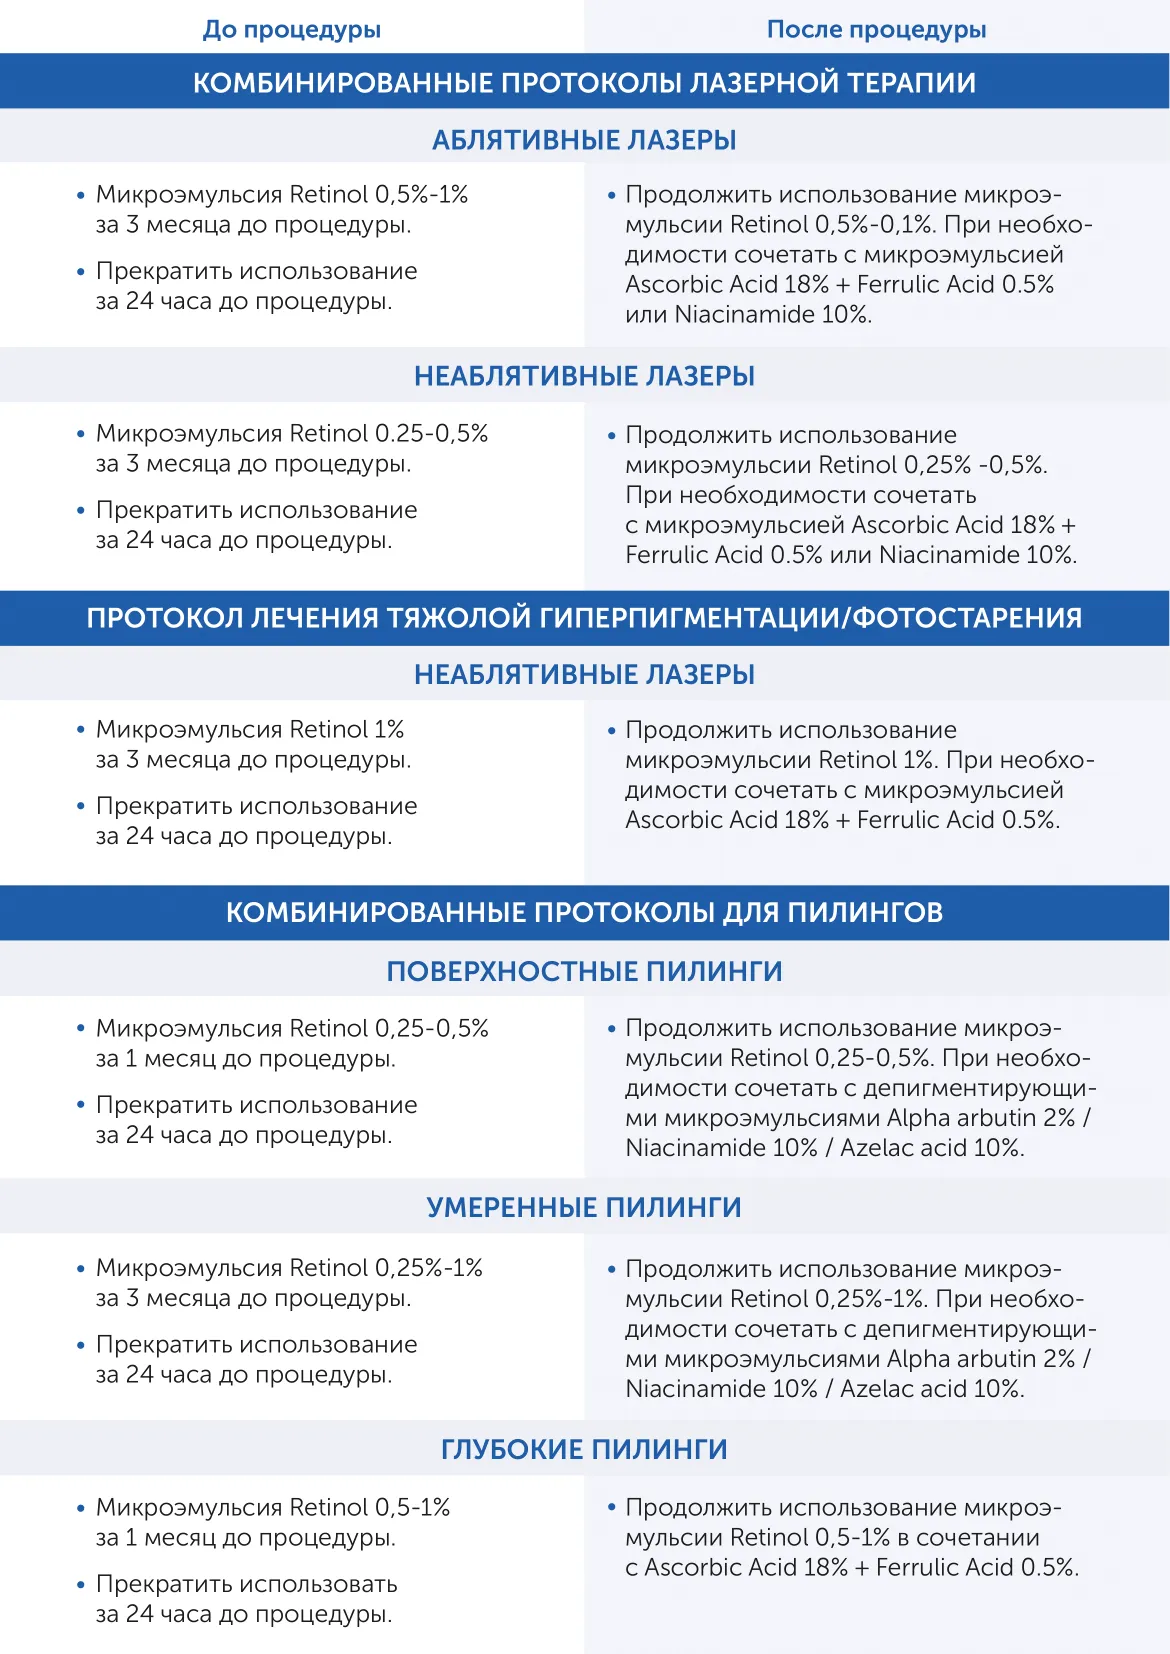

Микроэмульсия на основе 5% транексамовой кислоты, 2% арбутина MiChro™, 5% ниацинамида Tranexamic MiChro Skintellectual Solutions

Гиперпигментация, мелазма, воспалительные элементы, профилактика пигменатции после травматичных процедур

Микроэмульсия на основе 5% транексамовой кислоты, 2% арбутина MiChro™, 5% ниацинамидп MiChro™ разработанна для эффективной коррекции и уменьшения гиперпигментации. Мощная формула осветляет и выравнивает тон, помогает уменьшить покраснения, улучшает текстуру, укрепляет естественный барьер, предотвращая появление фотостарения. Эффективное действие микроэмульсии основано на запатентованном способе доставки MiChro™, что дает ей более глубокое пронивкновение в кожу и более длительное сохранение высокой концентрации активного ингредиента (до 24 часов).